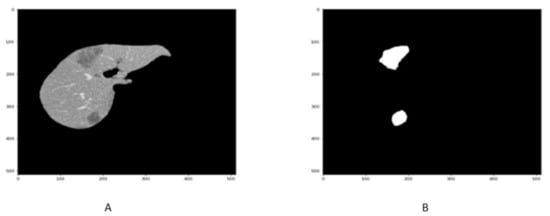

4.3. Tumor Segmentation Results

The qualitative and quantitative result of liver Tumor CT scan segmentation is shown in Figure 8 and in Table 3. The proposed technique has been obtained in terms of liver segmentation as assessed by DSC, accuracy, precision, specificity VOE, and RVD values. The Figure 8A,B and Table 3 highlight the better performance of proposed approach.

Figure 8.

Figure shows that the samples of Liver Tumor segmentation in (A,B).